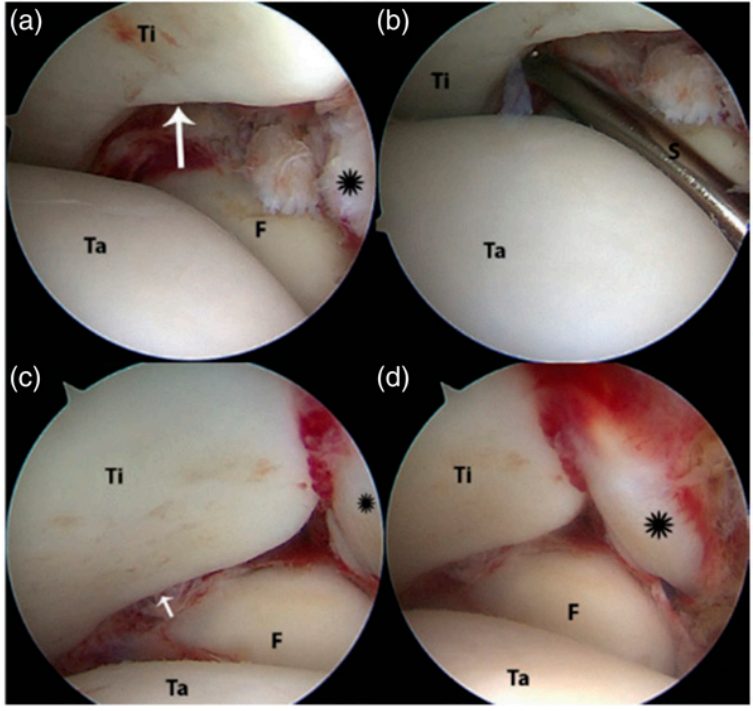

Рис. 18. Артроскопический вид повреждённого синдесмоза: a — внешний вид, b — положительный стресс-тест, c и d — этапы устранения подвывиха

Хронические повреждения

При хронических повреждениях артроскопия позволяет оценить положение малоберцовой кости во вырезке и стабильность голеностопного сустава. Несостоятельность синдесмотических связок часто выявляется при мануальном тестировании под артроскопическим контролем — например, при пробе сжатия (squeeze test) гипертрофированная синовиальная ткань выпячивается в полость сустава при компрессии малоберцовой кости к большеберцовой и исчезает при прекращении компрессии, что верифицирует нестабильность во фронтальной плоскости.

Целостность синдесмоза также можно оценить введением 3-миллиметрового зонда в дистальный межберцовый сустав с мягким вращением его вокруг продольной оси.

Последовательная диссекция связок показала, что для возникновения нестабильности синдесмоза во фронтальной плоскости необходимо повреждение ПНБМс, межкостной связки и ЗНБМС. Артроскопическая оценка такой нестабильности должна проводиться вдоль заднего края вырезки. Если нестабильность выявляется как кзади, так и кпереди, это указывает на сопутствующее повреждение дельтовидной связки.

Артроскопия также помогает выявить гипертрофию синдесмотических связок с развитием переднелатерального импинджмента.

В сравнении со стресс-рентгенографией, которая не могла достоверно отличить интактный синдесмоз от повреждения одной связки, артроскопическое зондирование позволяло дифференцировать изолированные повреждения ПНБМс или дельтовидной связки и различать различные паттерны последовательного повреждения связок.